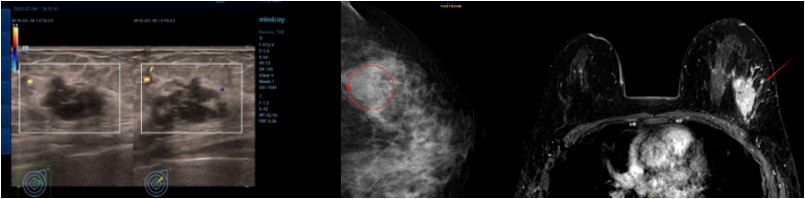

乳腺彩超:左侧乳腺实性结节(1-2点),28×18mm,BIRADS 4B类。左侧腋窝淋巴结肿大,15×11mm。

乳腺钼靶:左乳外上象限钙化灶及结节影,BI-RADS 4B类。

乳腺MRI:左乳外上象限肿块,大小约29mm×19mm,考虑乳腺癌,BI-RADS 6类。

乳腺彩超:左侧乳腺皮肤水肿增厚,约4.7mm。左乳部分切除术后,皮层明显增厚,左乳内结构显示不满意,BIRADS 0。右侧乳腺未见明显占位病变,BIRADS 1类。左侧腋窝区未见异常淋巴结。右侧腋窝淋巴结肿大,最大约33×15mm,皮质明显增厚,部分门型结构消失,性质待查。

乳腺MR:左乳上象限乳腺癌治疗后改变,病灶范围较前增大,较大范围约30mm×31mm×29mm;左侧乳腺多发结节、乳晕、皮肤增厚及右腋窝增大淋巴结,大者直径24mm,考虑转移。右乳多发囊性病灶,右乳背景多发轻度强化,考虑良性改变,BI-RADS 3类。

PET-CT:考虑左乳皮皮肤转移伴炎症可能;右侧腋窝淋巴结转移。余未见明显异常。